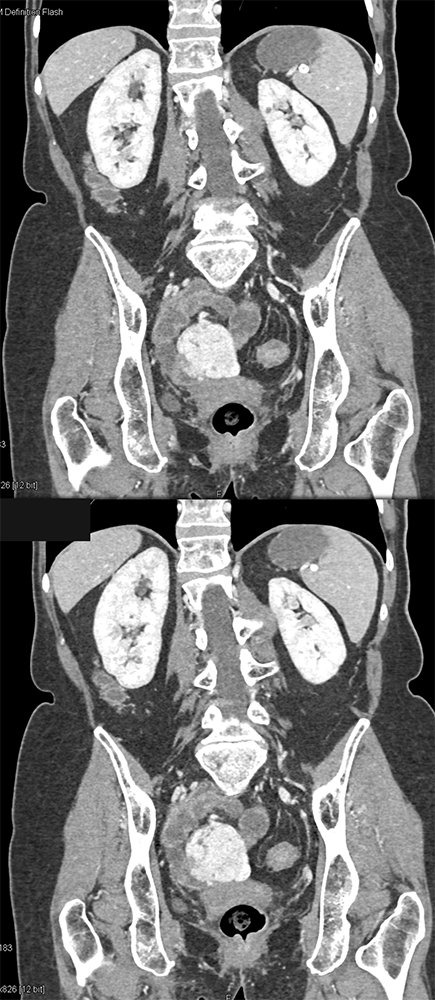

RCC Metastatic to Small Bowel ![]() |

![]() |